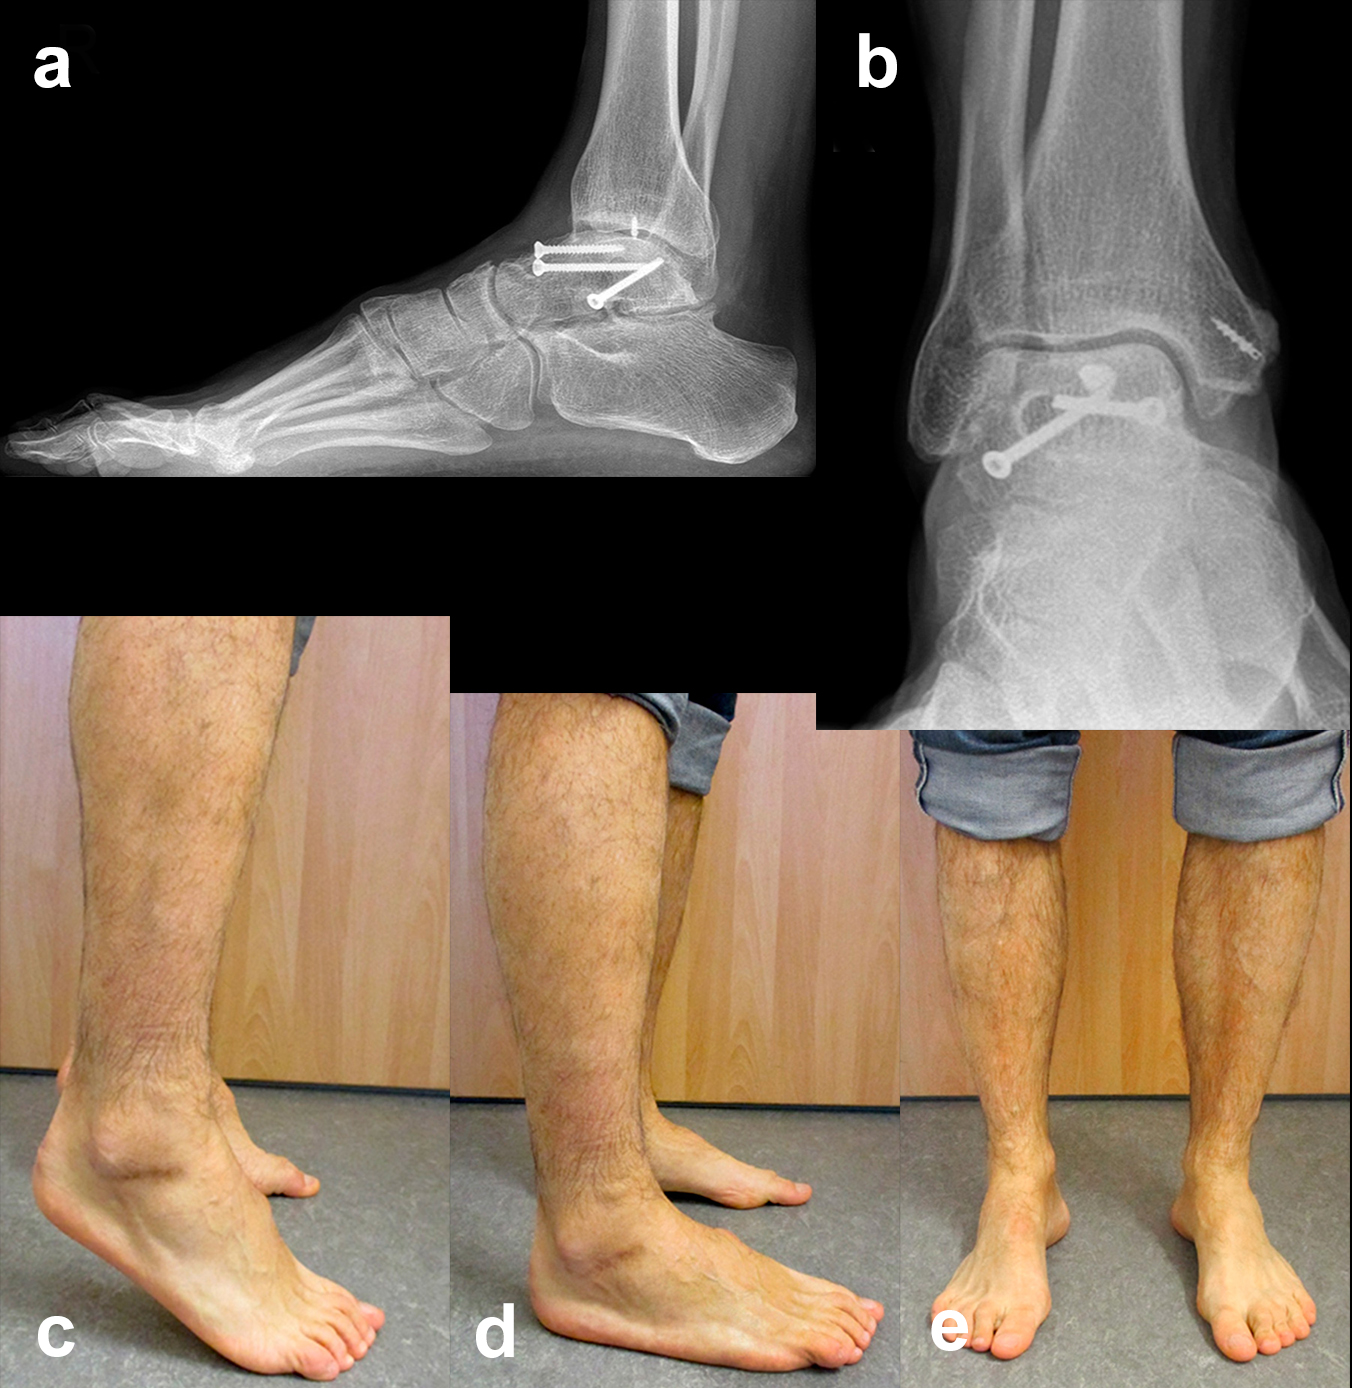

Die Nachbehandlung erfolgt prinzipiell frühfunktionell mit 15-20 kg Teilbelastung für 12 Wochen bei zentralen Talusfrakturen im abnehmbaren Spezialstiefel.  Aktive und passive Bewegungsübungen für das obere und untere Sprunggelenk (incl. Chopart-Gelenk) beginnen, je nach Weichteilverhältnissen, ab dem 2. postoperativen Tag, um die postoperative Funktionseinschränkung durch Verwachsungen minimal zu halten (Abb. 19).

Zur Vollansicht und zum Lesen der Bildbeschreibung bitte das Bild anklicken.